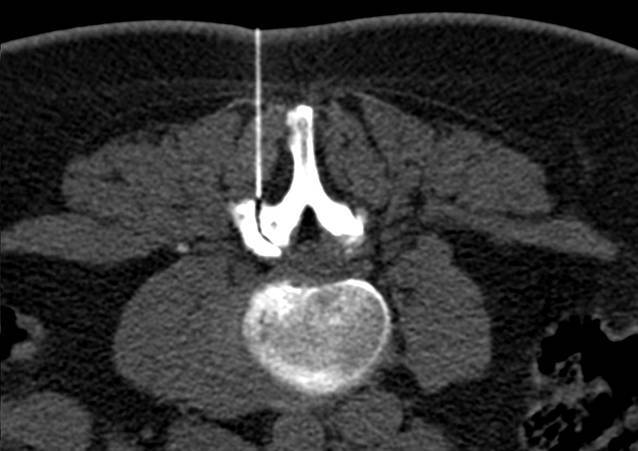

Alle Interventionen wurden in Bauchlage durchgeführt. Die Planung der Untersuchung erfolgte jeweils an einem angepassten Planungsscout auf der zuvor bekannten Interventionshöhe. Anschließend wurde die Interventionsplanung in der entsprechenden CT-Schicht durchgeführt. Nach sorgfältiger lokaler Desinfektion, steriler Vorbereitung und Markierung der Punktionsstelle wurde unter CT-Kontrolle in Low-dose-Technik unter Einsatz von CareDose die Intervention durchgeführt (Tab. 1). Nach Maßgabe des behandelnden Radiologen erfolgte die Überprüfung der Nadelposition während der Intervention, und die Verteilung des Medikamentengemisches wurde dokumentiert (Abb. 1 und 2). Die Interventionen wurden entweder an einem Siemens Emotion 6, an einem Siemens Somatom Definition 64 oder an einem Siemens Definition AS 64 durchgeführt.

In Abhängigkeit von der körperlichen Fülle des Patienten wurde eine 22G-Nadel mit einer Länge von 90 mm oder 120 mm verwendet (Becton Dickinson SA, S. Agustin del Gualdix, Spain). Als Lokalanästhetikum wurde 2 %iges Meaverin eingesetzt (Meaverin 2 %, Puren Pharma, Munich, Germany). Als Kontrastmittel zur Dokumentation der Verteilung des Medikamentengemisches wurde Iohexol (Accupaque 240, GE Healthcare, Munich, Germany) verwendet, als Kortikoid wurden in Abhängigkeit vom Patientengewicht, Verträglichkeit sowie Vorerkrankungen 10–20 mg Triamcinolon injiziert (Volon A, (2 ×) 10 mg, Dermapharm AG, Gruenwald, Germany). Nach der Durchführung der Intervention wurden die Patienten gebeten, jeweils eine Stunde im Institut zu verweilen. Die anschließende Verabschiedung erfolgte vom durchführenden Arzt, um sicherzustellen, dass keine Nebenwirkungen aufgetreten sind. Unmittelbar nach der Therapie und im Abstand von 1 bis 14 Tagen (Durchschnitt: 8 Tage) wurde erneut der Schmerzscore mittels VAS bestimmt.